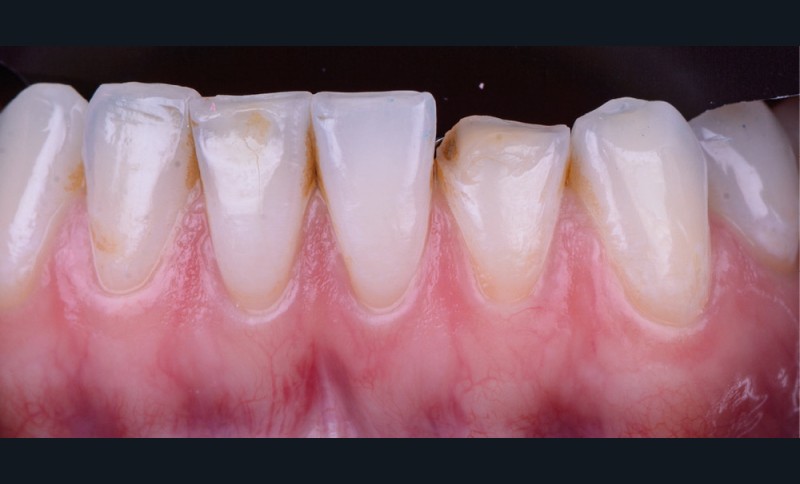

Il existe aujourd’hui sur le marché des résines composites fluides chargées, résistantes mécaniquement et qui présentent de bonnes propriétés optiques. Le choix d’une résine qui présente de bonnes propriétés optiques impose néanmoins une photopolymérisation en fine épaisseur. Ainsi, dans le cas d’une perte de substance supérieure à 2 mm, il est préférable de reconstruire la surface en plusieurs incréments [2]. L’injection de résine au travers de la clé ne concerne ainsi que la couche la plus superficielle.

Afin d’obtenir un comportement optique le plus proche possible de celui de la dent naturelle, l’auteur recommande de réaliser le corps de la dent au préalable à l’aide d’un composite de restauration plus saturé. C’est uniquement la couche la plus superficielle qui est injectée. La technique d’injection de composite nécessite le respect d’un protocole strict et comporte quelques difficultés qu’il convient d’anticiper.